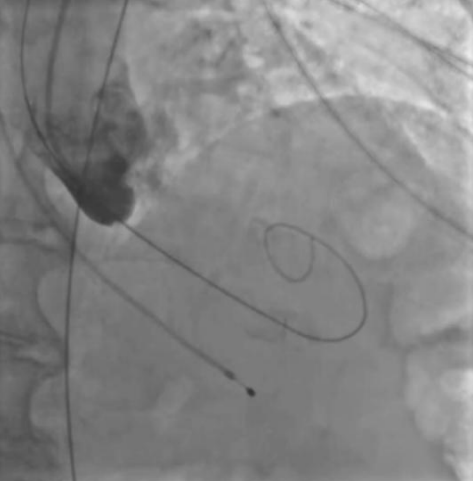

Введение. Болезнь Фабри (БФ) может имитировать гипертрофическую кардиомиопатию и сопровождаться обструкцией выносящего тракта левого желудочка или средне-желудочковой обструкцией. В случае наличия у пациента внутриполостной обструкции и рефрактерной к медикаментозной терапии сердечной недостаточности может быть рассмотрена септальная редукция.

Краткое описание. Нами представлен случай этаноловой септальной аблации (ЭСА) у пациента женского пола с генетически подтвержденной БФ и симптоматической многоуровневой внутриполостной обструкцией. Ей проведена транскатетерная ЭСА с последующим устранением средне-желудочковой обструкции и обструкции выносящего тракта левого желудочка. Гемодинамический эффект сохранялся в течение последующих 3 мес. наблюдения.

Дискуссия. Наш случай иллюстрирует факт, что ЭСА может быть эффективной и безопасной в устранении обструкции у пациентов с БФ при условии дальнейшего наблюдения за внутрисердечной гемодинамикой.